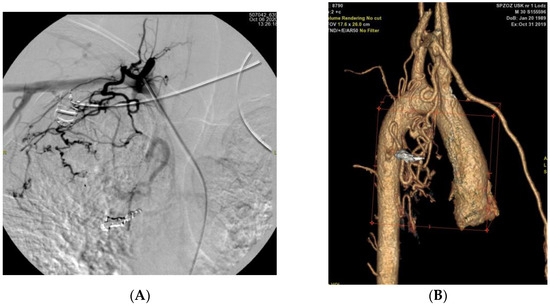

Cystic Artery Bleeding: Imaging Insights and Systematic Review of Endovascular Management

Background: Cystic artery bleeding (CAB) is a rare but potentially life-threatening condition. Its etiologies span iatrogenic trauma, inflammatory diseases, and trauma, often presenting variably as hemoperitoneum, upper gastrointestinal bleeding, or hemorrhagic shock. The clinical heterogeneity of CAB complicates its diagnosis, necessitating a high index of suspicion and reliance on imaging modalities, particularly computed tomography (CT), for accurate identification of bleeding sources and differentiation from other causes of abdominal pain. Methods: This pictorial essay highlights key imaging findings in CAB and pseudoaneurysms, emphasizing the role of ultrasound, CT, and digital subtraction angiography (DSA) in diagnosis and management planning. Additionally, a systematic review of transcatheter arterial embolization (TAE) is presented, consolidating data from 64 studies encompassing 90 patients. Results: The review evaluates patient demographics, etiologies, clinical presentations, and procedural outcomes, underscoring TAE’s high efficacy and safety as a first-line treatment. Conclusions: The findings reinforce the importance of early diagnosis and tailored intervention strategies to optimize outcomes in CAB management. Full article

Show Figures

Figure 1